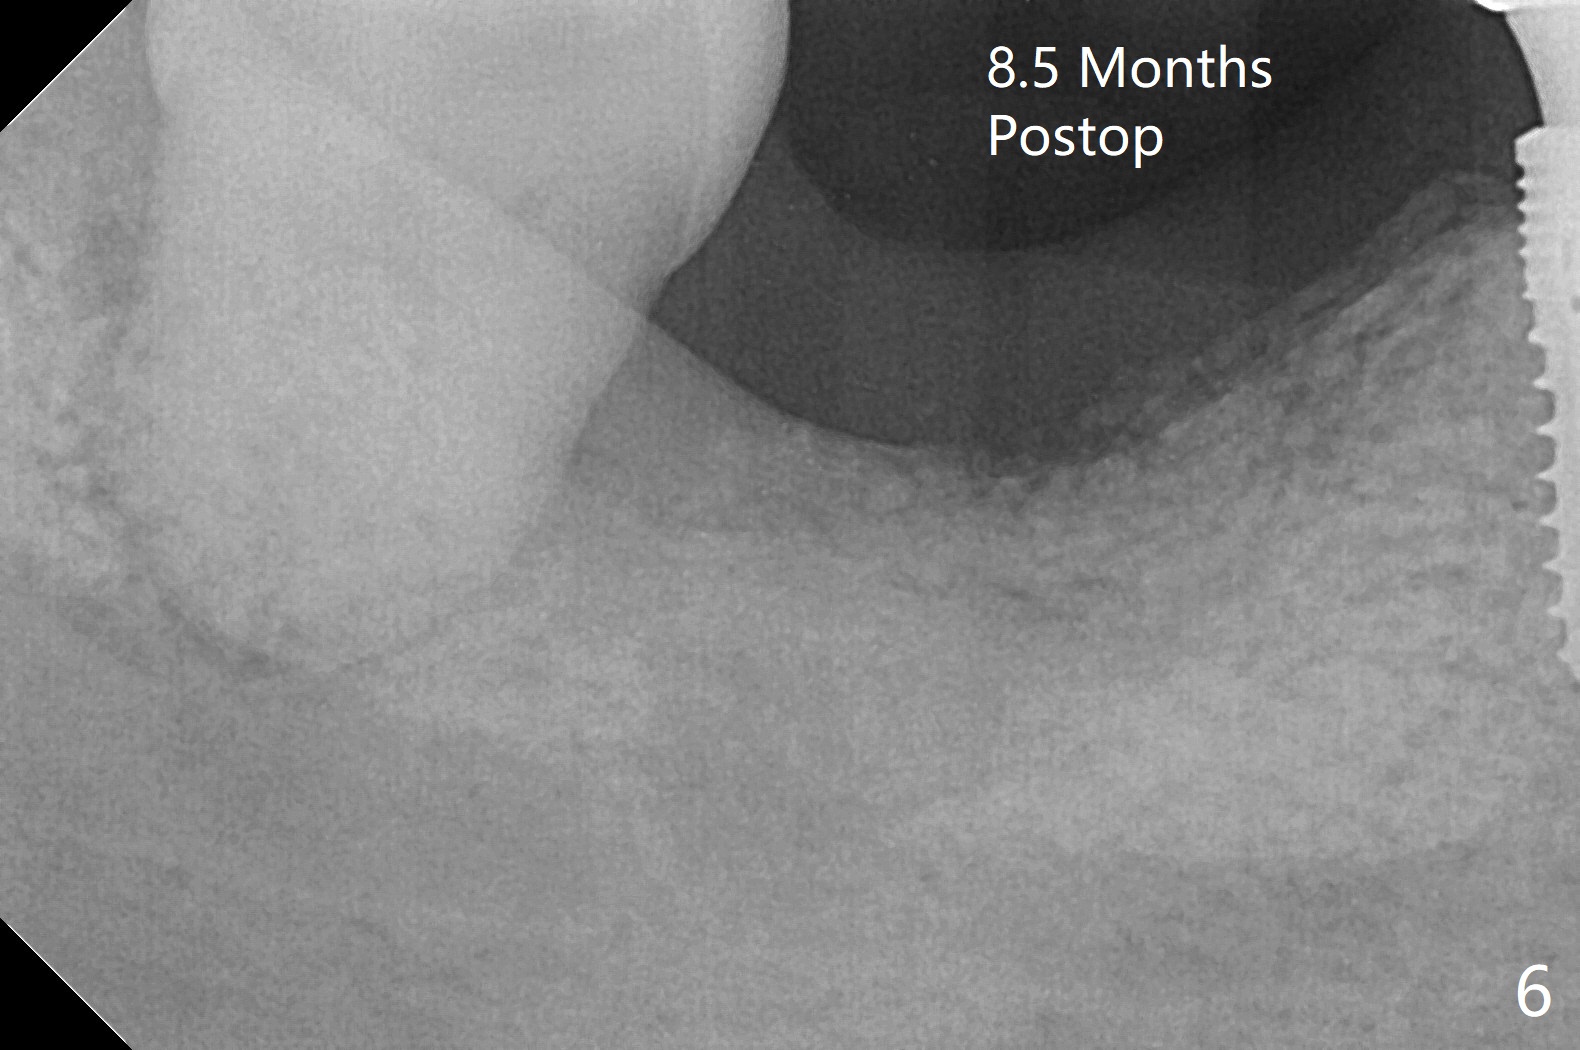

Although the bony socket is shallow, the soft tissue one remains deep at #31 with gingival recession (Fig.1 *). The deep soft tissue socket with hemorrhage after extraction presents difficulty in debridement of granulation tissue apically. After placement of allograft (Fig.3 *) and overlying collagen membrane (Fig.2 C), the socket is closed with 4-0 Chromic gut suture. In fact, there is ~ 2 mm granulation tissue left (Fig.4 red (yellow line: upper border of the Inferior Alveolar Canal)). To reduce socket shrinkage, the tooth #32 is not extracted. The collagen membrane has lost 1 week postop (Fig.5). More sutures should have been used, preferably using Human Amnion Chorion Allgraft as a membrane. The latter promotes wound healing. The bone graft also seems to have lost in 8.5 months (Fig.6). A short implant will be placed mesially and obliquely (Fig.7).